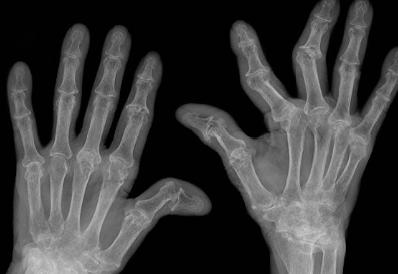

이러한 증상이 6주 이상 지속되면 류마티스 관절염을 의심해야 합니다. 의사와 상담하여 혈액 검사나 X-ray 검사 등을 통해 정확한 진단을 받아야 합니다.

류마티스 관절염은 관절 주위를 둘러싸고 있는 활막이라는 조직의 염증으로 인해 발생하는 만성 염증성 질환입니다. 이 질환은 활막이 존재하는 모든 관절, 즉 움직일 수 있는 거의 모든 관절에서 발생할 수 있으며, 손과 발의 작은 관절에 좌우 대칭적으로 관절염이 생기는 것이 특징입니다. 류마티스 관절염은 주로 40대에서 70대 사이의 여성에게 많이 발생하며, 우리나라의 유병률은 약 0.5~1.0%로 추정됩니다.

류마티스 관절염의 정확한 원인은 아직 밝혀지지 않았지만, 유전적 요인과 환경적 요인의 상호작용에 의해 자가 면역 반응이 일어나는 것으로 생각됩니다. 즉, 인체의 면역체계가 자신의 몸을 비정상적으로 공격하여 염증이 발생하는 것입니다. 이러한 염증은 관절의 연골과 뼈를 손상시키고, 관절의 변형과 기능 장애를 초래합니다. 또한 전신적인 증상으로 피로감, 발열, 식욕 부진, 체중 감소 등을 유발할 수 있습니다.